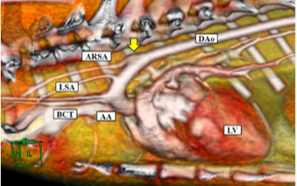

このため、動物医療センターには最新の放射線治療装置をはじめとする高度医療機器が設置され、学生実習をサポートできる専任の獣医師、動物看護師の指導の下、最先端の知識や技術を習得できるようになっています。